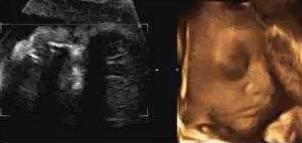

【在妇产科医院,你可以看到这样的胎宝】

麻麻,我正在挠耳朵